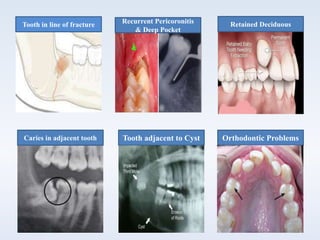

 Tooth in line of fracture

 Recurrent pericoronitis

 Deep periodontal

pocket

 Prior to orthodontic

treatment

 Prevention of root

resorption and caries

 Retained Deciduous

teeth

 Management of cysts

and tumors

Tooth in line of fracture

Orthodontic ProblemsTooth adjacent to CystCaries in adjacent tooth

Retained DeciduousRecurrent Pericoronitis

& Deep Pocket